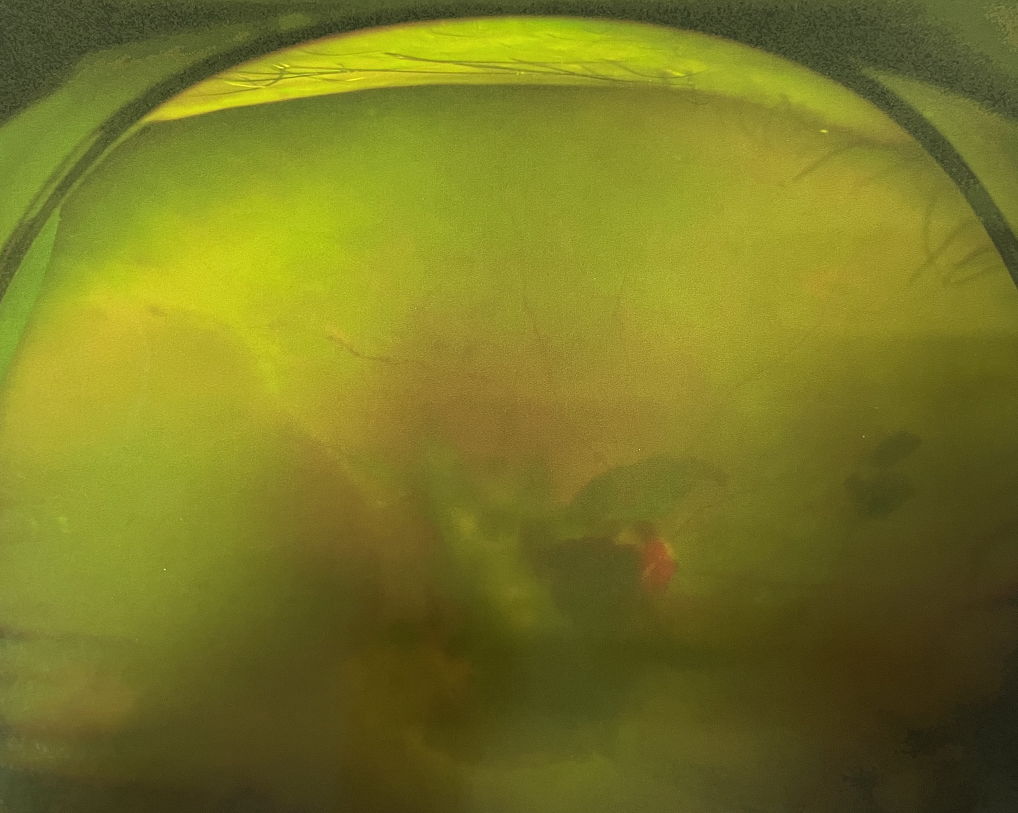

眼底出血多指玻璃體內(nèi),眼睛更深處的視網(wǎng)膜出血。通常情況下,肉眼難以發(fā)現(xiàn)眼底出血,而且發(fā)病初期眼睛也無(wú)明顯癥狀,只有借助專業(yè)的眼底檢查儀器才能觀察到異樣。那么眼底出血嚴(yán)重嗎?

誘發(fā)眼底出血的原因眾多,常見的有全身性血管病和血液病、視網(wǎng)膜血管異常、機(jī)械性阻塞、炎癥性疾病或免疫復(fù)合物侵犯血管壁等。

眼底出血嚴(yán)重嗎?其中,“三高”患者、高度近視患者和滲出性或濕性老年黃斑變性患者是眼底出血的高發(fā)人群。

醫(yī)生提醒,一旦眼睛出現(xiàn)視力下降、視物變形、視野缺損或眼前有黑影等視覺“異常”的情況,應(yīng)及時(shí)到醫(yī)院進(jìn)行眼底檢查,及早發(fā)現(xiàn),及早治療,以免貽誤病情。

眼底出血嚴(yán)重嗎?對(duì)于已出現(xiàn)黃斑水腫、視網(wǎng)膜新生血管的患者,根據(jù)眼底血管造影、oct等檢查結(jié)果,給予玻璃體腔注射抗VEGF藥物及激光治療,可以減輕黃斑水腫,使視網(wǎng)膜新生血管消退,以免進(jìn)一步發(fā)生玻璃體出血、視網(wǎng)膜脫離等嚴(yán)重并發(fā)癥的出現(xiàn)。對(duì)于玻璃體出血者,傳統(tǒng)認(rèn)為玻璃體出血3-6個(gè)月不吸收再進(jìn)行手術(shù)干預(yù),但近年來(lái)因?yàn)轱@微手術(shù)設(shè)備及玻璃體切割技術(shù)已非常成熟,故對(duì)于1個(gè)月不吸收的玻璃體出血者就可以考慮手術(shù),即手術(shù)時(shí)機(jī)應(yīng)該具體情況具體分析,因人而異。